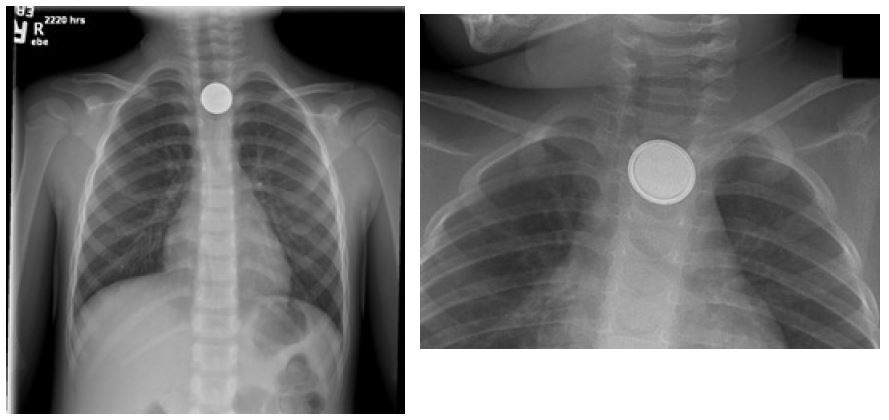

Anteroposterior and lateral plain films of the chest should be obtained.2,21 Also obtain abdominal radiographs in a patient without symptoms but with a history of button battery ingestion.2,21 The presence of a double ring or halo sign on an anteroposterior projection and a step-off sign on a lateral projection will help to differentiate a button battery from a coin.2,20-22 (See Figure 1.) Small, thin batteries may not have a reliably visualized step-off or halo sign because of their size.20

Figure 1. Coin and Button Battery Appearance on Anteroposterior Chest X-Ray |

Left: Coin in upper esophagus; Right: Button battery on X-ray; note “double halo” Images courtesy of: Chad D. McCalla, MD, and Crick Watkins, DO. |